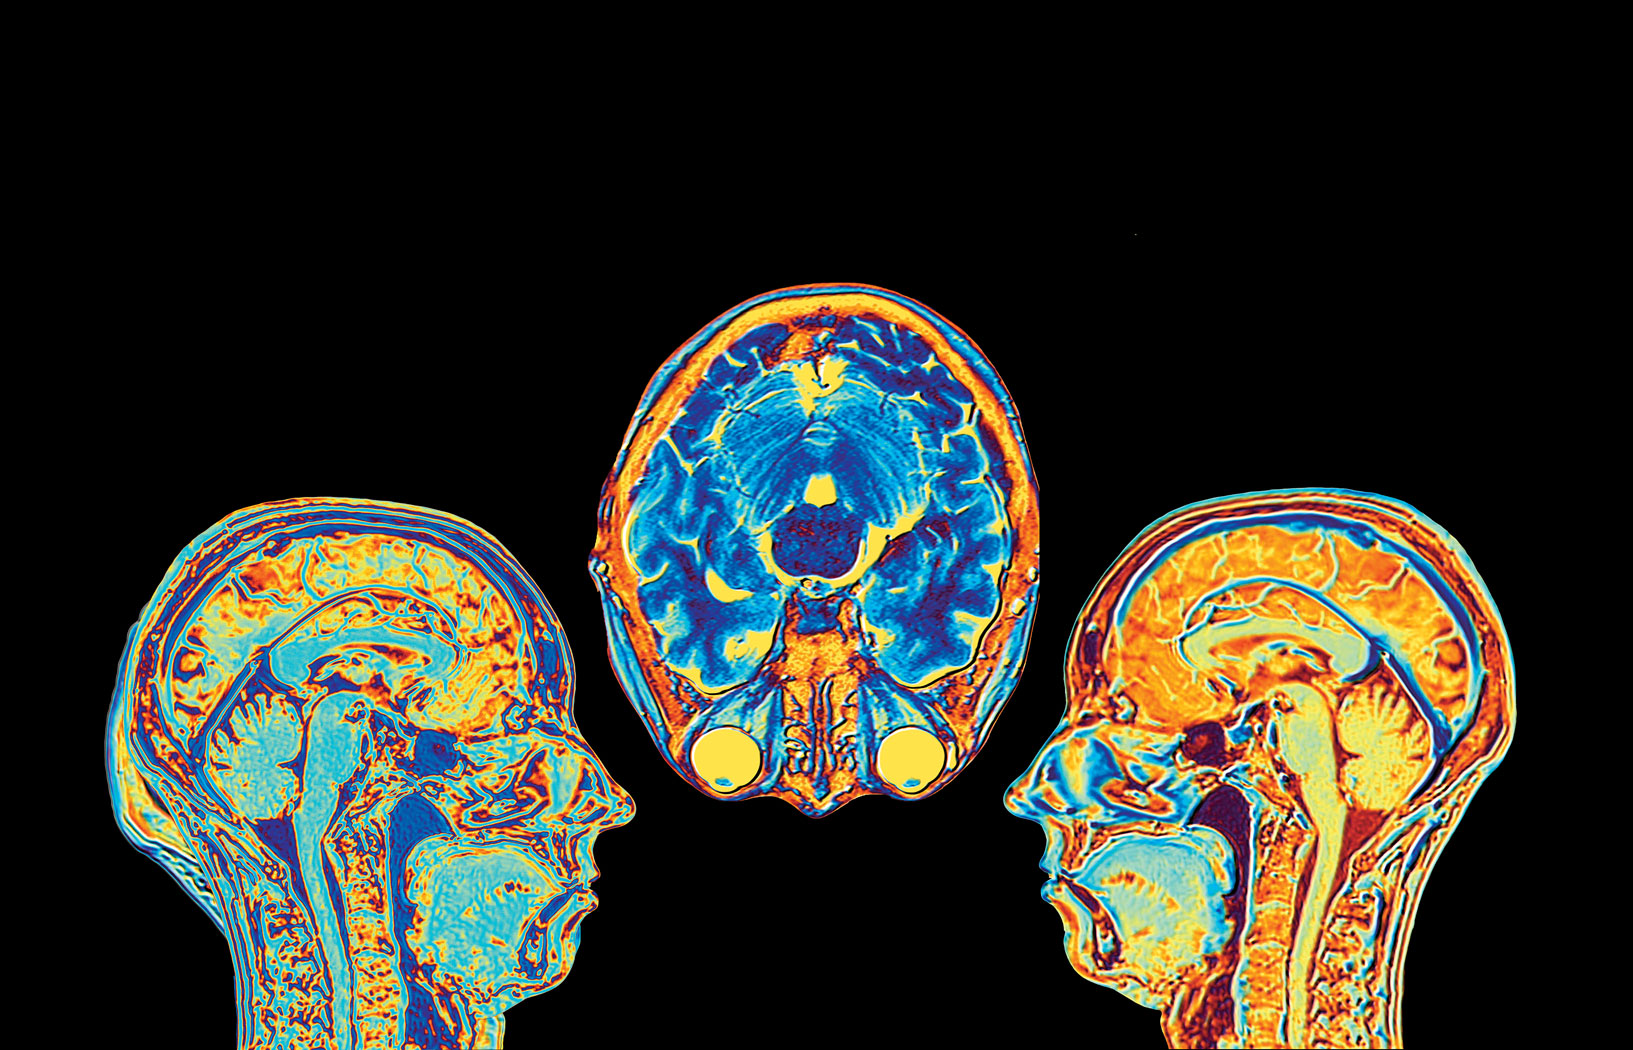

„Badaniom kory mózgowej i jej roli w chorobach psychicznych poświęciłam prawie całą zawodową karierę.” „Badaniom kory mózgowej i jej roli w chorobach psychicznych poświęciłam prawie całą zawodową karierę.” Getty Images

BARBARA K. LIPSKA: – Pod wpływem immunoterapii, na którą zareagowałam wyjątkowo silnie, doszło do stanu zapalnego oraz obrzęku w mózgu. Objął on całą przednią część kory mózgowej i – dosłownie – oszalałam. Straciłam umiejętności logicznego myślenia i oceny sytuacji, pamięć i możliwość wyrażania emocji. Stałam się podejrzliwa, miałam paranoję, że inni czyhają na moje życie, że chcą mnie otruć. Nie odczuwałam empatii, więc zachowywałam się okrutnie w stosunku do męża i rodziny – krytykowałam, wymagałam, krzyczałam, nie rozumiałam ich stresu i przerażenia, że mogę wkrótce umrzeć. Te zachowania są regulowane przez płaty czołowe, które przestały funkcjonować. Gdyby obrzęk nastąpił w tylnej części mózgu, regulującej oddychanie i pracę serca, mogłabym nie przeżyć. Na szczęście wysokie dawki sterydów zmniejszyły stan zapalny i po około dwóch miesiącach powoli wróciłam do normalności.